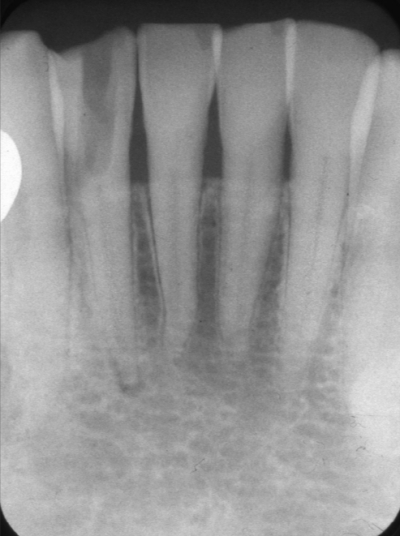

74 歳の女性。下顎右側側切歯の鈍痛を主訴として来院した。感染根管治療を行うこととし、根管を探索したが見つからなかった。治療中のエックス線画像を別に示す。

根管の探索方向を確認するために追加すべきなのはどれか。2つ選べ。